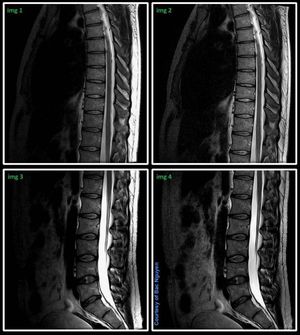

MR Neuo Spine Imaging @ 3T Skyra Take a closer look at these 4 images, they have same window level, exact same parameters for comparison. Which images do you prefer for thoracolumbar spine? What do you think was done? #s_mri #siemens #mri #neuro

hello,i like img 2,what technology is used? normalize? i am rookie